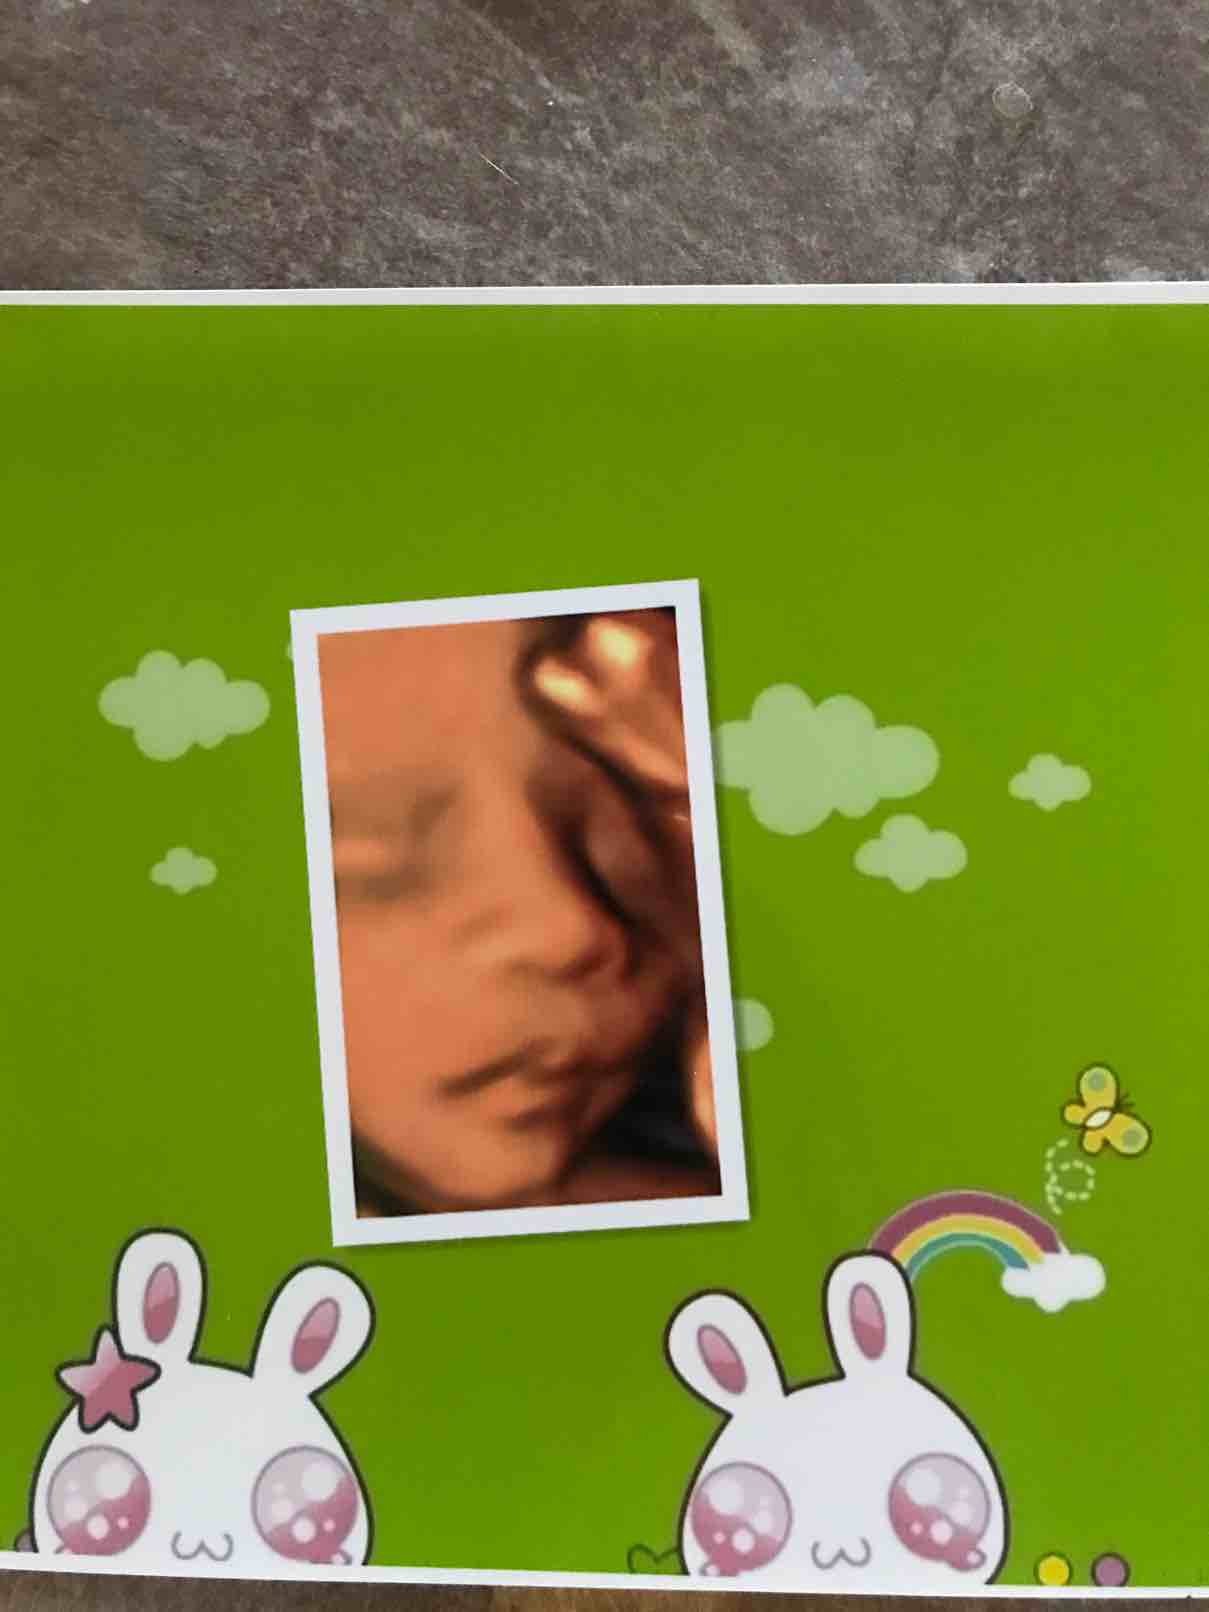

昨天24周➕2,去做的四维大排畸,一个多月前预约的9.27日下午1:40做,宝宝很配合,顺利通过,还有宝宝可爱的照片,看着好喜欢 宝宝发育的很好,比孕期大了一周,唯一不好的就是胎盘还是很低,从12周检查胎盘低置宫颈内口,到现在24周多,依然在宫颈内口,医生也说,涨上去的可能不大了,就是后期多注意点吧!

宝宝发育的很好,比孕期大了一周,唯一不好的就是胎盘还是很低,从12周检查胎盘低置宫颈内口,到现在24周多,依然在宫颈内口,医生也说,涨上去的可能不大了,就是后期多注意点吧!

下面附上 我家小多多的可爱照片

下面附上 我家小多多的可爱照片

挡着一只眼睛呢?好可爱

恭喜恭喜,宝宝好可爱,我猜是儿子

宝宝这么清楚了,漂亮